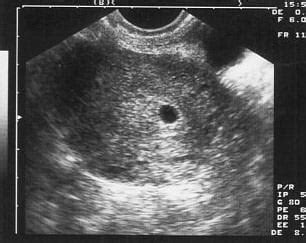

Az 5. hét végétől már hüvelyi ultrahanggal is kimutatható a terhesség, de ilyenkor még csak a petezsák látszik (egy fekete, nagyjából kör alakú folt az ultrahang felvételen), a benne lévő embrió nem. Ezért nem kell megijedni, ha a leleten azt olvasod, hogy élő embrió nem látható. Csak a 8-10. hét körül várható az embrió láthatóvá válása.

A petezsák, vagy orvosi nevén gestational sac, az a folyadékkal telt üreg, amely a méh üregében jön létre, és amelyben a fejlődő embrió és a magzatvíz elhelyezkedik. Ez az első olyan struktúra, amelyet megbízhatóan azonosítani lehet a transzvaginális ultrahanggal, általában már a terhesség nagyon korai szakaszában. A petezsákot a trofoblaszt sejtek hozzák létre, miután a megtermékenyített petesejt sikeresen beágyazódott a méh nyálkahártyájába.

A petezsák megjelenése tehát kritikus jelentőségű. Két alapvető információt szolgáltat: először is, megerősíti a méhen belüli terhesség tényét, kizárva (vagy legalábbis csökkentve) a méhen kívüli terhesség gyanúját. A kismamák gyakran sürgetik az első ultrahangot, de a türelem elengedhetetlen, mivel a petezsák csak egy bizonyos méret elérése után válik láthatóvá. A petezsákot általában a terhesség 5. hetében lehet először detektálni, ha a számítás a legutolsó menstruáció első napjától indul. Ez az időpont körülbelül 3 héttel az ovuláció és a megtermékenyítés után van. Ha az ultrahangot túl korán végzik - például a 4. hét végén -, könnyen előfordulhat, hogy a petezsák még nem látszik, ami felesleges aggodalmat okozhat. Az orvosok ezért gyakran javasolják, hogy a kismama várja meg legalább a betöltött 5. hetet, vagy még inkább a 6.

Az ultrahangon a petezsák egy jellegzetes, fekete vagy sötét, kerek, folyadékkal telt területként jelenik meg. Ezt a sötét területet egy vastag, világosabb, hiperechogén gyűrű veszi körül. Ez a gyűrű valójában a méh nyálkahártyájának reakciója a beágyazódásra, és a trofoblaszt sejtek helyét jelzi. A kettős decidualis zsák jel (DDSS) megléte jelzi, hogy a beágyazódás sikeres volt, és a terhesség a méh megfelelő rétegében fejlődik.